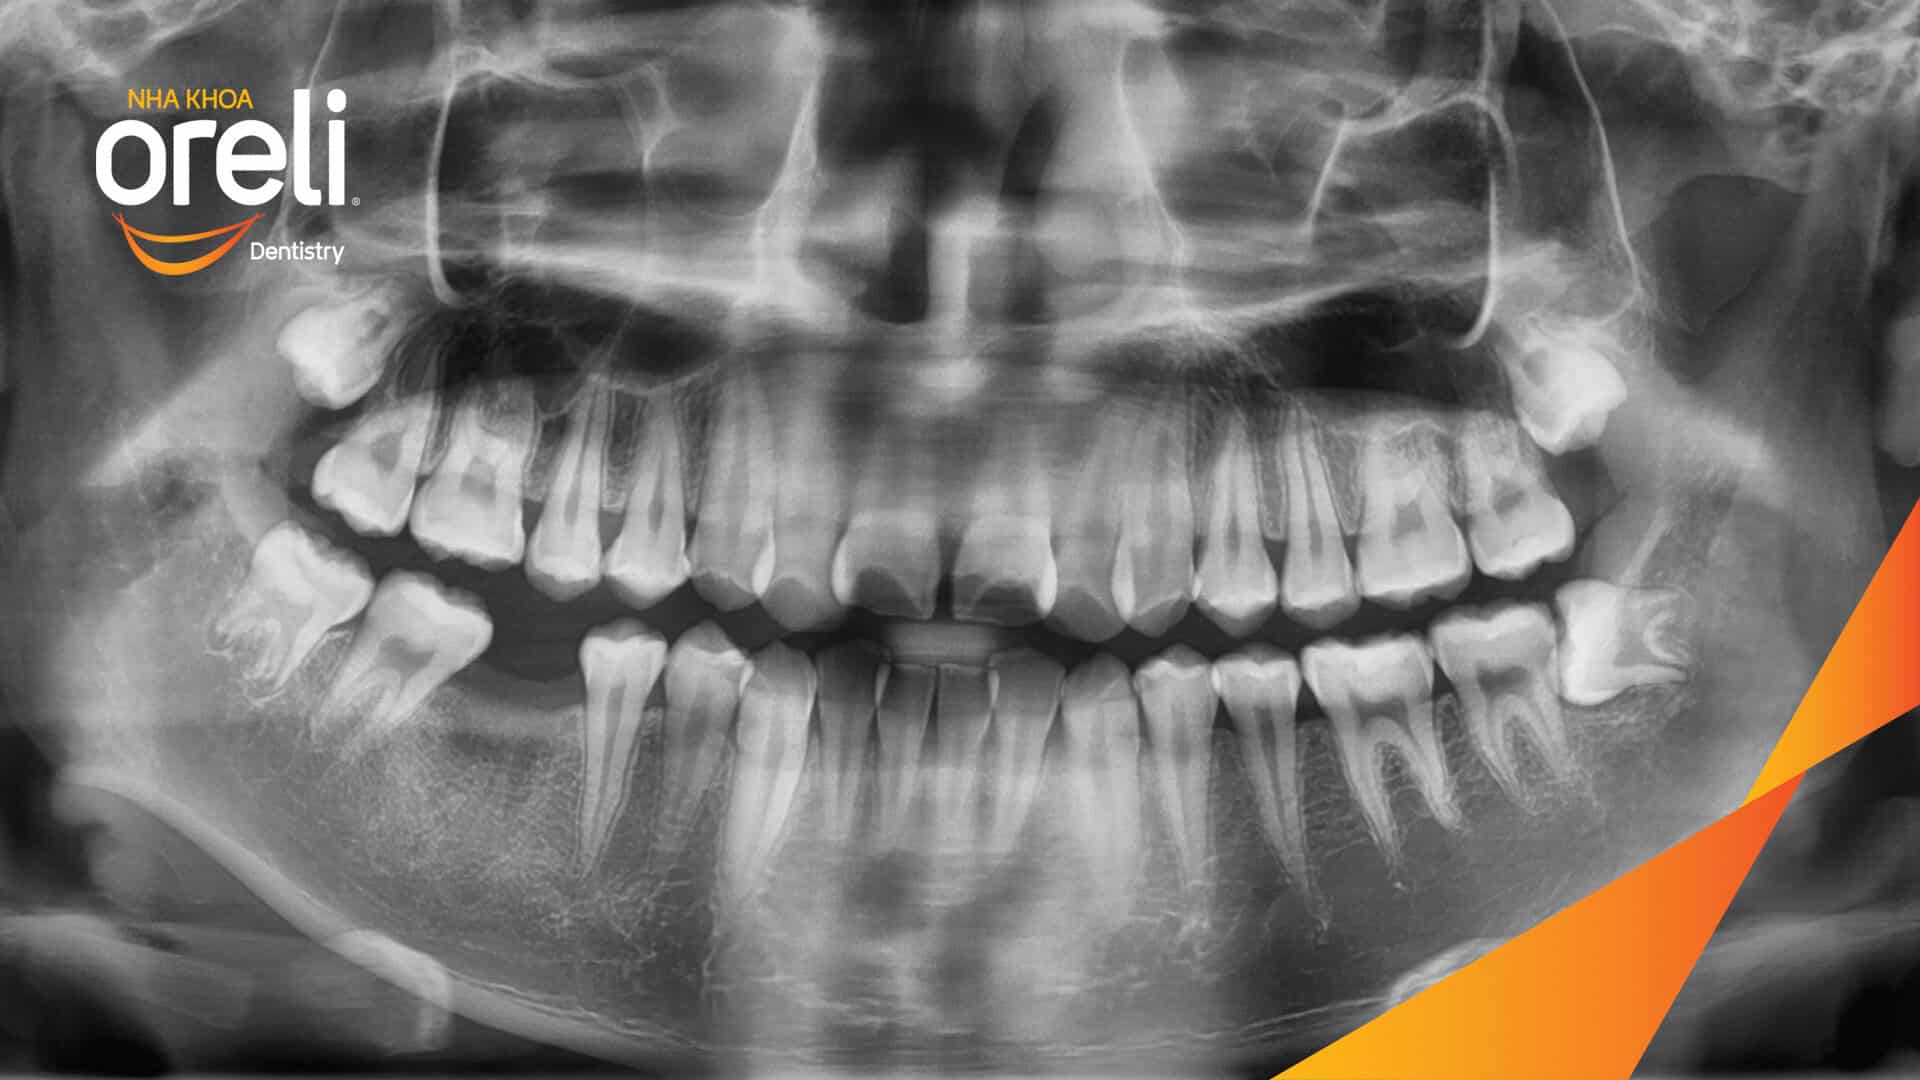

Niềng răng hô nhổ 2 răng số 4 hàm trên trường hợp 2 răng cửa hàm dưới? Case thực tế tại Oreli Niềng răngChen chúc Xem thêm